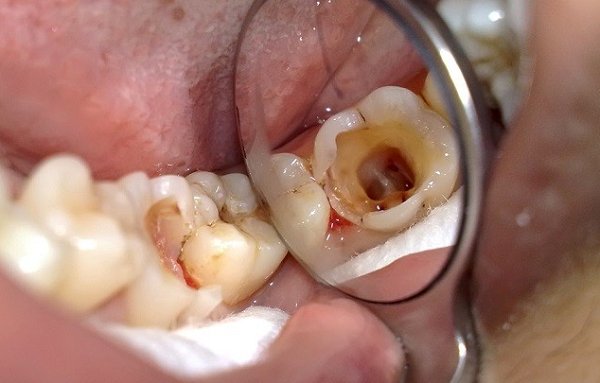

Hình ảnh răng bị kém khoáng hóa gây nên sâu, vỡ, hỏng cần loại bỏ

Hậu quả là: răng dễ mòn, sâu, vỡ vụn dần dưới lực ăn nhai thông thường – đặc biệt là ở răng hàm lớn.

Cấu trúc men răng yếu, dễ vỡ, dễ tổn thương